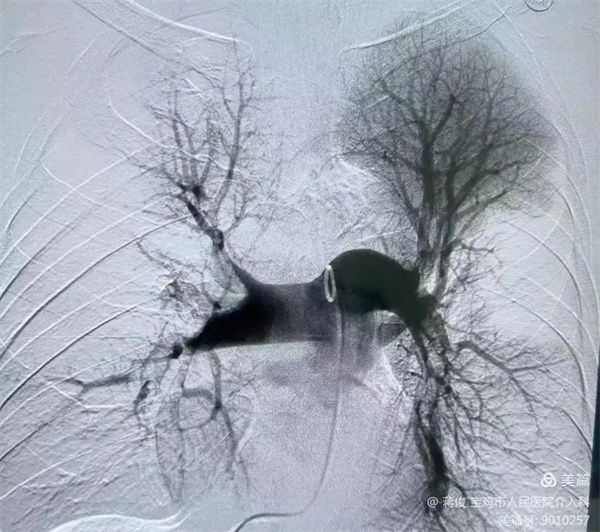

肺動脈DSA造影提示肺動脈主干及分支大量血栓,予以肺動脈造影、血栓溶解、肺動脈碎栓